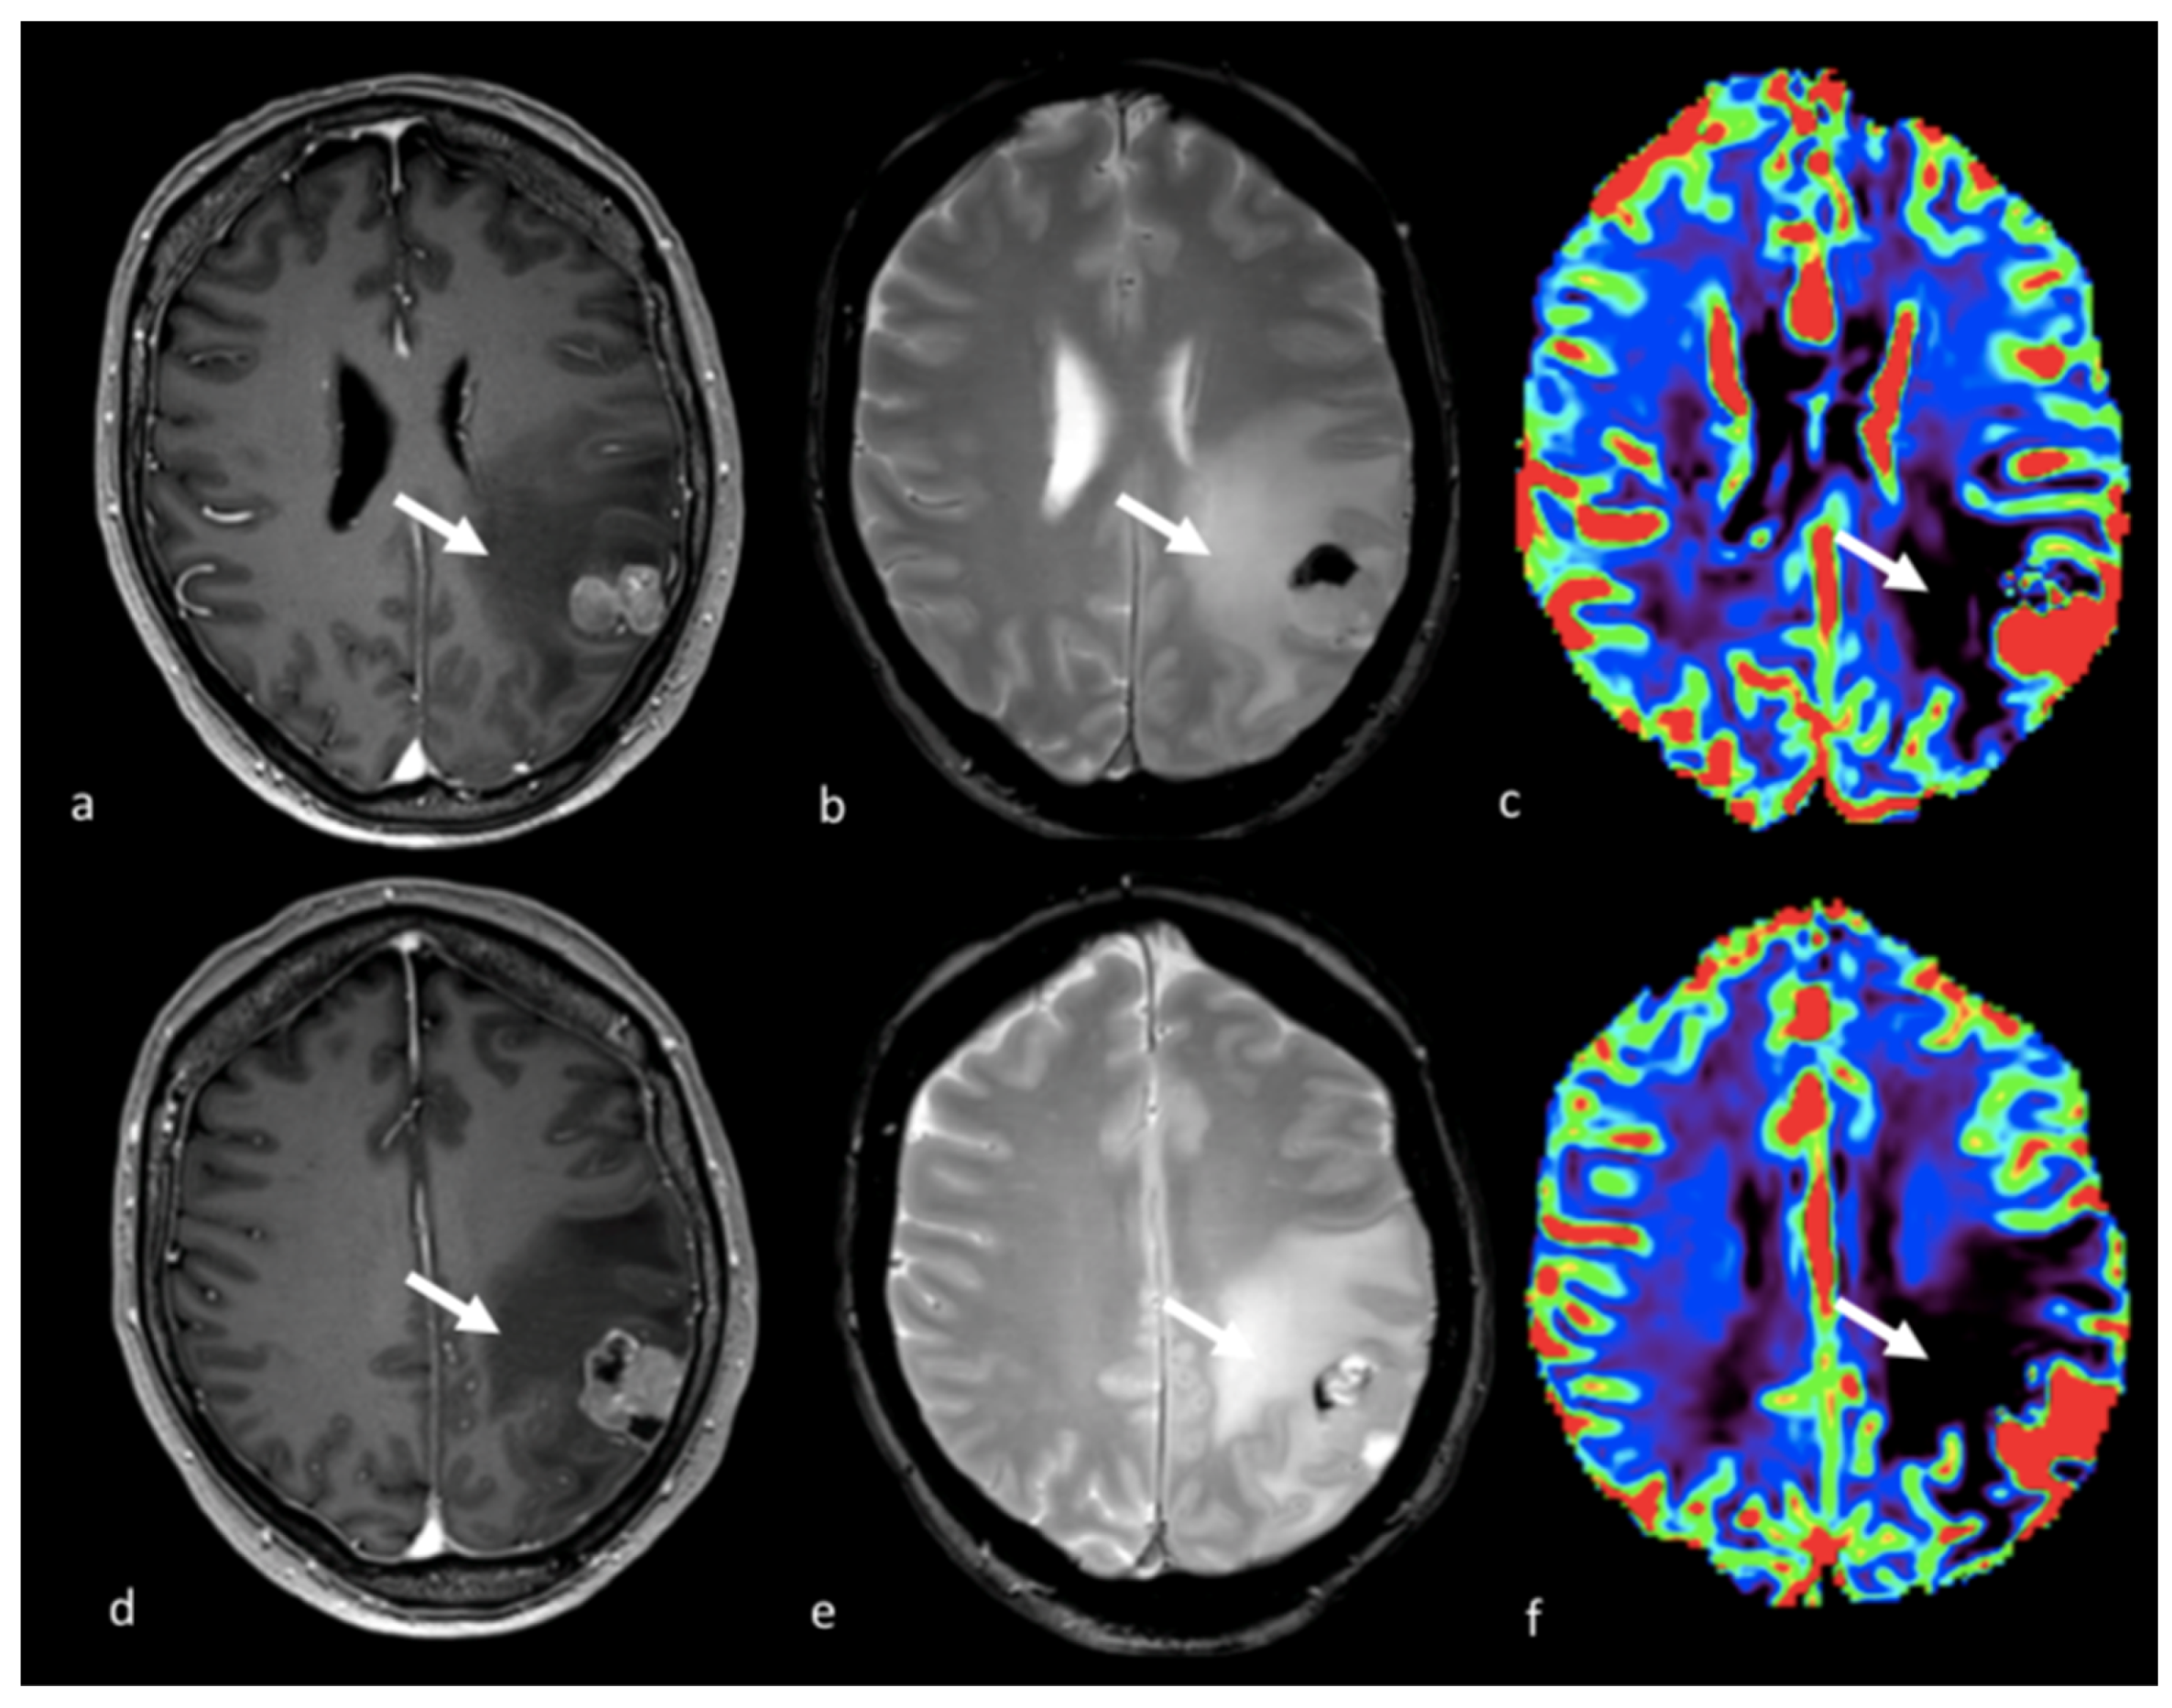

3.3.1. Dynamic Susceptibility Contrast-Enhanced Perfusion

3.3.2. Dynamic Contrast-Enhanced Perfusion Imaging

3.3.3. Arterial Spin Labeling